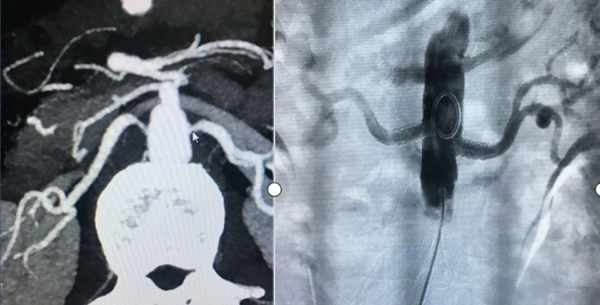

肾血管相关检查:包括超声波、CT血管成像或核磁共振等影像学检查,以确认肾动脉狭窄的情况。

介入治疗:适用于病变部位可达的情况。常用的介入治疗方法是经皮肾血管成形术,可以消除或缓解肾动脉狭窄,从而减轻高血压程度。